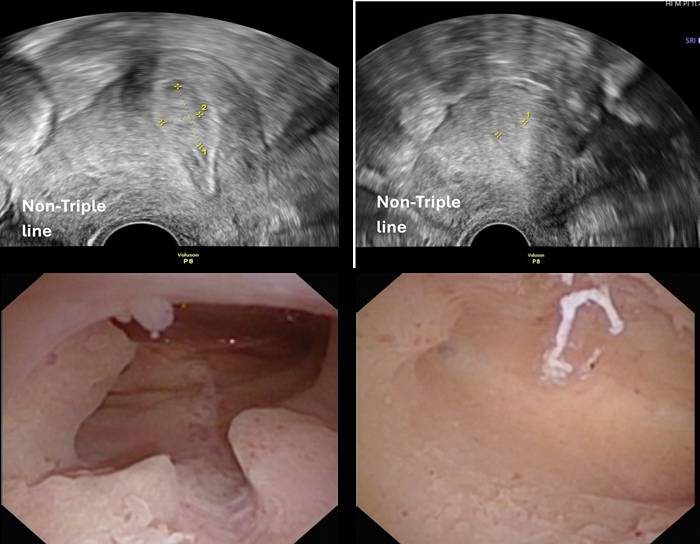

以下是一個真實的案例,多發性息肉合併發炎(左圖),在息肉切除後追蹤,超音波顯示非三條線,子宮鏡檢查呈現多發性微息肉及內膜炎(右圖),仍需以口服抗生素治療。

(圖說:手術前之陰道超音波(左上)及子宮鏡呈像(左下):多發性子宮內膜息肉及內膜炎。圖片提供/宜蘊醫療)

(圖說:手術後之陰道超音波(右上)及子宮鏡呈像(右下):多發性微息肉及內膜炎。圖片提供/宜蘊醫療)